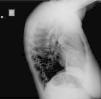

Two active fixation leads (85 cm Medtronic CapSureFix Novus® 5076) were implanted via the right femoral vein using peel-away introducers and positioned in the right ventricular septum and right atrial roof. Acute thresholds were 0.6 V for the right ventricle and 2.0 V for the right atrium, with impedances of 520 and 600 Ω, respectively. The R wave was measured at 5.5 mV and the P wave at 2.6 mV. A coronary sinus sheath (57 cm Medtronic Attain Command® with SureValve 6250VI-EHXL) was introduced over a deflectable electrophysiology catheter (Bard Dynamic XT) and advanced to the coronary sinus. Venography was performed (Figure 1) and a posterolateral vein was selected for placement of an 88 cm Medtronic Attain Ability® 4196 bipolar lead (Figures 2–4). These leads, as well as the coronary sinus sheaths, were selected because of their longer length, as the patient's height was 174 cm. A femoral pocket was created in the upper leg. The three leads and the generator were fixed to the muscle under the aponeurosis, using silk sutures.